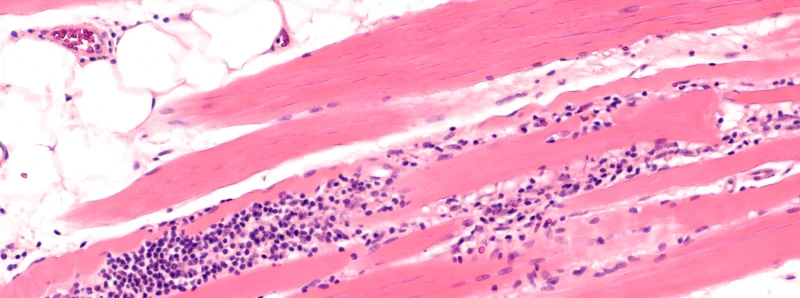

Pain has long been overlooked as a disease symptom in patients with myositis; therefore, little is known about myositis-related pain. Our currently active projects aim to investigate potential mechanisms of pain in patients with myositis by understanding the link between the myositis-related pain and neural dysfunction and disease related inflammation in the muscles and fascia.